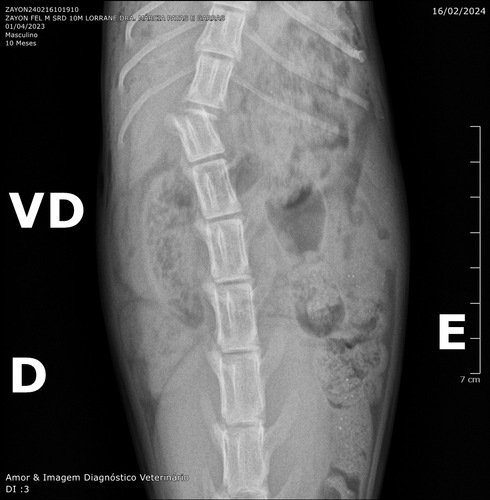

Olá, me chamo Ana Paula e criei essa vaquinha para este gato que resgatei das ruas, o qual chamei carinhosamente de Zayon. Não sabemos ao certo o que lhe aconteceu, o que sabemos é que Zayon está com uma fratura na coluna. Porém, por um milagre de Deus, ele responde a estímulos na perna, e consegue controlar o xixi, ou seja, a sua medula não foi afetada na fratura, o que torna de Zayon um verdadeiro milagre!

Levamos ele no veterinário, e agora ele precisa da sua ajuda para fazer uma cirurgia que pode tirar sua dor e possivelmente fazer com que ele volte a andar. O valor pedido corresponde ao valor da cirurgia, anestesia e dos dias em que ele precisará ficar internado.